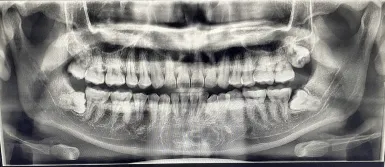

ก็เลยลองไปหาหมอฟันเอกซเรย์ดู เรียบร้อยย 4 ซี่!!!

และ ณ วันนั้นก็ลองถอนฟันคุดด้านบนออกมา 1 ซี่ โคตรเจ็บ! นี่ขนาดยังไม่ผ่า

ฟันคุดควร Clear ให้หมดก่อนอายุ 25 ปี เพราะกระดูเราจะยังไม่แข็งมาก เอาหละเหลืออีก 2 ปี กับฟันคุด 3 ซี่ที่เหลือ